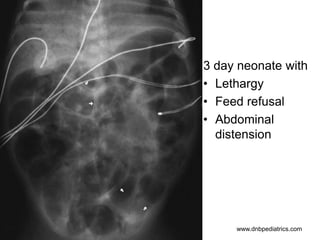

3 day neonate with

• Lethargy

• Feed refusal

• Abdominal

distension

1. What stage of NEC is depicted in the

X-ray?

2. What is the radiological feature of Bell

stage III NEC?

3. Name two more conditions associated

with pneumatosis intestinalis?

1. NEC Stage II

2. Pneumoperitoneum

3. Any two of following

Hirschsprung's

disease, Pseudomembranous

enterocolitis, Neonatal ulcerative colitis,

Ischemic bowel disease